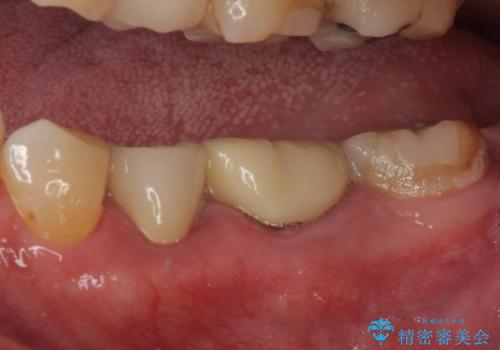

- 奥歯の詰め物が外れてしまったとのことで来院された患者様です。

レントゲン写真より、既に根管治療がされている歯であり、根尖部に骨透過像が認められました。

特に症状はありませんでしたが、根管治療を希望されたため、まずは根管治療を行うこととしました。

根管治療の際に、咬み合う上顎の銀歯が内側に入り込んでいることも気になるとのことであったため、部分矯正を行い、その後上下を同時に補綴治療することとしました。

部分矯正を行うと咬み合わせが定まらないことがありますが、今回は矯正治療後に上下補綴治療を行ったため、安定した咬み合わせにて仕上げることができました。